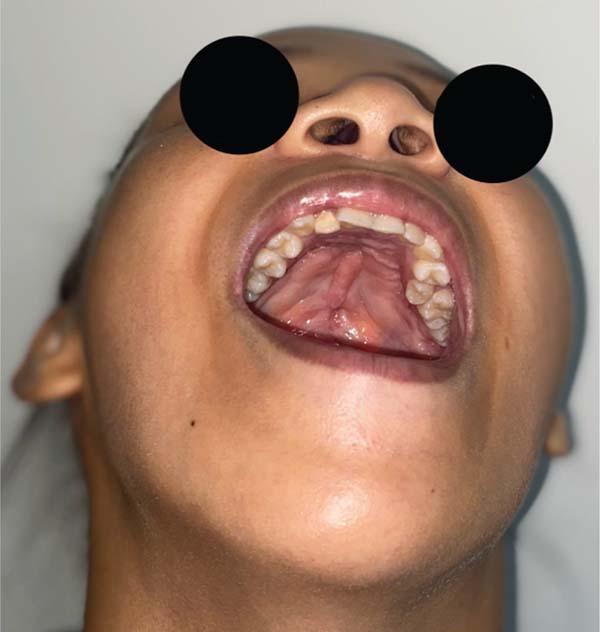

Further analysis revealed that one of these patients had a behavioral disorder with repetitive hand-to-mouth movements, as reported by the mother. In the second case, preoperative photographs revealed a velopalatine fossa and inadequate dissection by the surgeon, which contributed to fistula formation (►Figs. 4–11).

In the analysis of the cases of fistula in zone II, we identified a behavioral disorder in one subject, with a diagnosis of mild autism and maternal reports of repetitive hand-to-mouth movements, and, in another subject, a velopalatine fossa in preoperative photographs, indicating inadequate dissection as the cause of the condition. It is crucial to study ONF cases individually to understand the contributing factors and optimize the surgical approach to reduce its incidence.